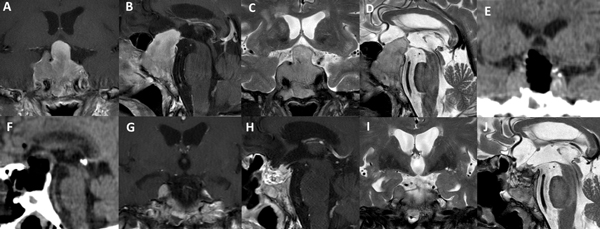

Existen situaciones que contraindican relativamente el uso de esta técnica y precisa un abordaje “extendido”: adenoma en reloj de arena, alto grado de extensión supraselar (e.g. invasión del III ventrículo), extensión para-selar (e.g. englobamiento carotideo), consistencia dura o fibrosa del tumor (Figura 6).

Figura 6. Paciente de 62 años, acromegálica, con adenoma gigante Hardy C y Knosp 4. No fue candidata a abordaje de Guante Blanco. Se utilizó un abordaje extendido para su tratamiento. A-D: RM preoperatoria. E-F: TC del primer día postoperatorio. G-J: RM postoperatoria.